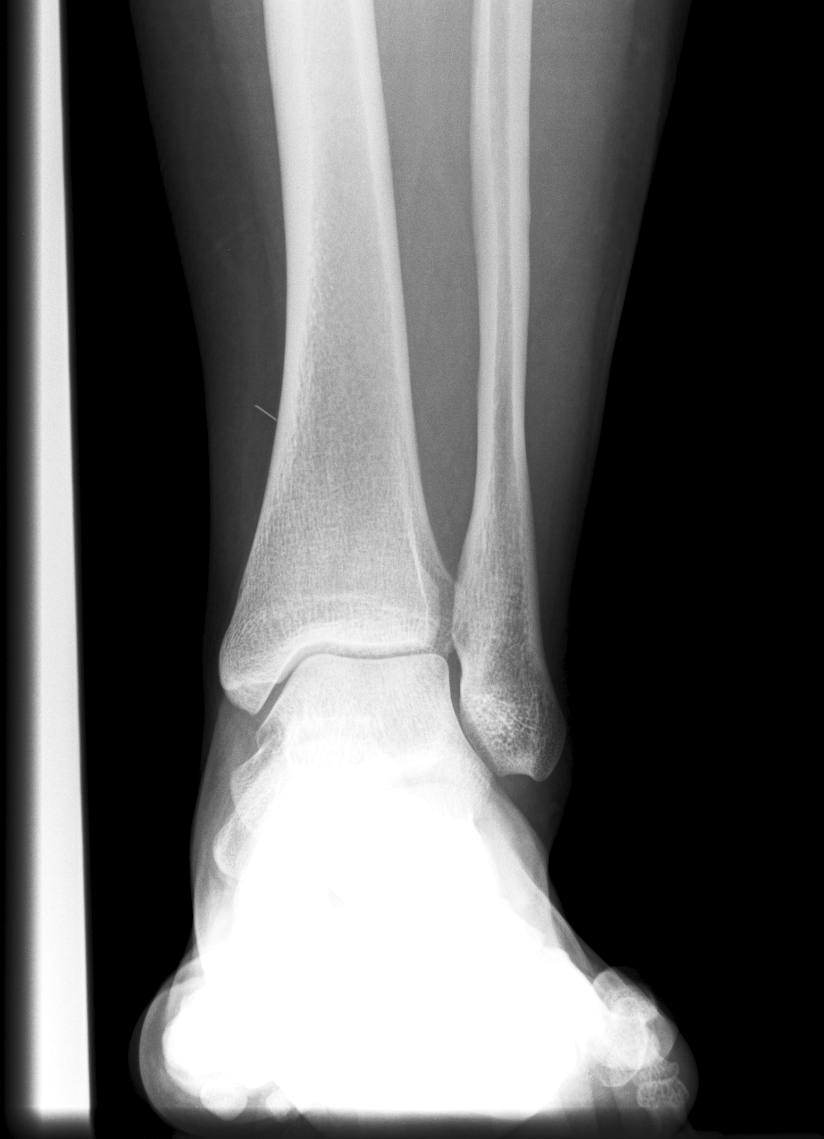

Findings

Bone

Growth plates, ossification centers, apophyses

Joints and alignment